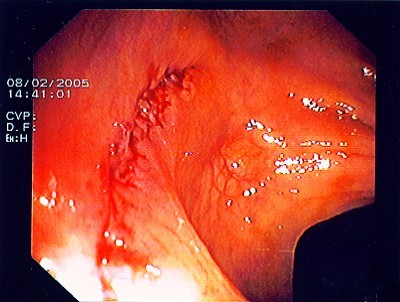

Gut sichtbarer Blutstrahl nach Abtragung eines Polypen

Sichere Blutstillung durch einen Metallclip